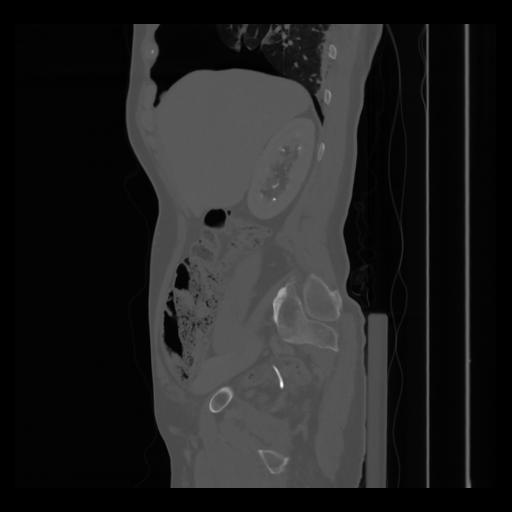

36 CUERPO,CE,Sagittal,3.000,CUERPO,Sagittal,